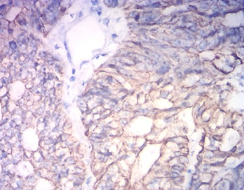

IHC    1/200 - 1/1000